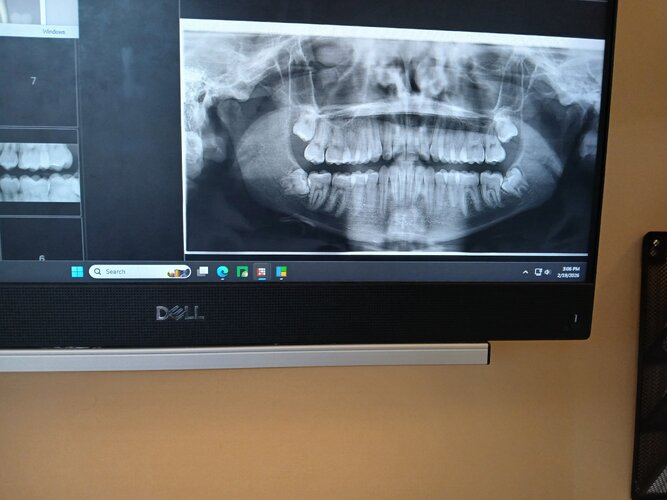

I got a scan of my teeth and the dentist noticed my lower jaw wisdom teeth are facing horizontally and they told me that all of my wisdom teeth would need to be removed because so. The root of the wisdom teeth are coming pretty close to an artery in my jaw they said. Would there be any reason not to get them removed?